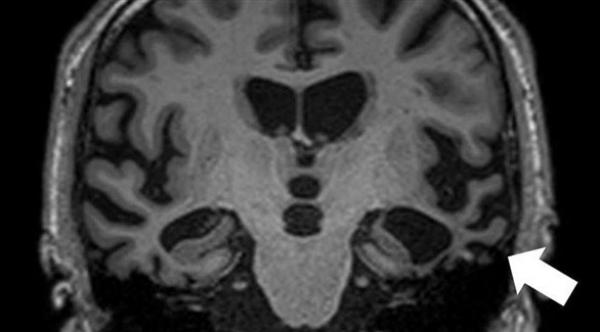

أوردت مجلة "سنيورين راتغيبر" الألمانية أن سبب مرض الخرف الجبهي الصدغي Frontotemporal dementia، تلف الخلايا العصبية في الفص الجبهي الصدغي للدماغ.